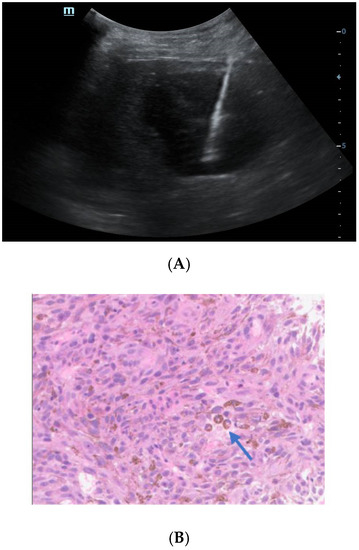

Ultrasound-Guided Coarse Needle Biopsy Diagnosed Isolated Hepatic Malignant Melanoma with Undetermined Origin in TB Patient: A Case Report

Chen, K.; Dong, Y.; Zhang, W.; Han, H.; Mao, F.; Zhang, H.; Wang, W. Ultrasound-Guided Coarse Needle Biopsy Diagnosed Isolated Hepatic Malignant Melanoma with Undetermined Origin in TB Patient: A Case Report. Diagnostics 2023, 13, 42. https://doi.org/10.3390/diagnostics13010042